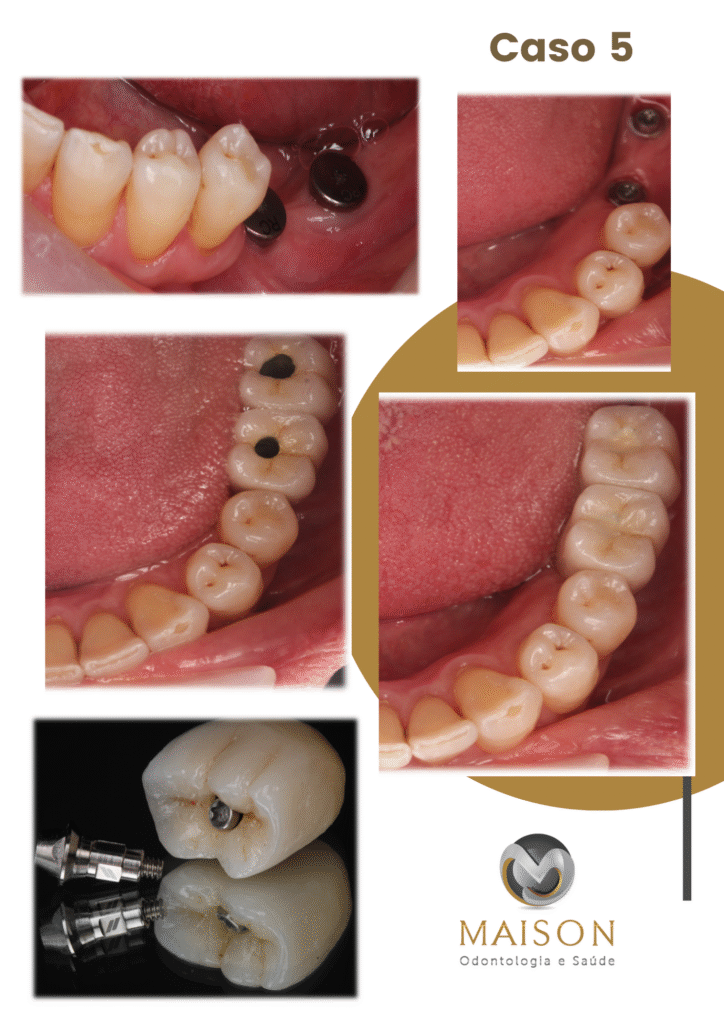

Transformação do Sorriso

Veja o que Nossos Pacientes

25 Anos de Experiência

Transformando Sorrisos

Com mais de 25 anos de experiência na área odontológica, o Dr. Giancarlo, Dra Morgana e equipe se destacam como um profissionais altamente qualificados e comprometidos com a saúde bucal de seus pacientes. Reconhecidos por sua abordagem cuidadosa e profissionalismo exemplar, eles se tornaram referência na área por oferecer tratamentos eficazes e humanizados.

- Técnicas Avançadas de Reabilitação Oral: Implantes Unitários, Múltiplos, Overdenture, Protocolo, Técnica Facco no osso Zigomático; realizamos todos o tipos de próteses sobre implante.